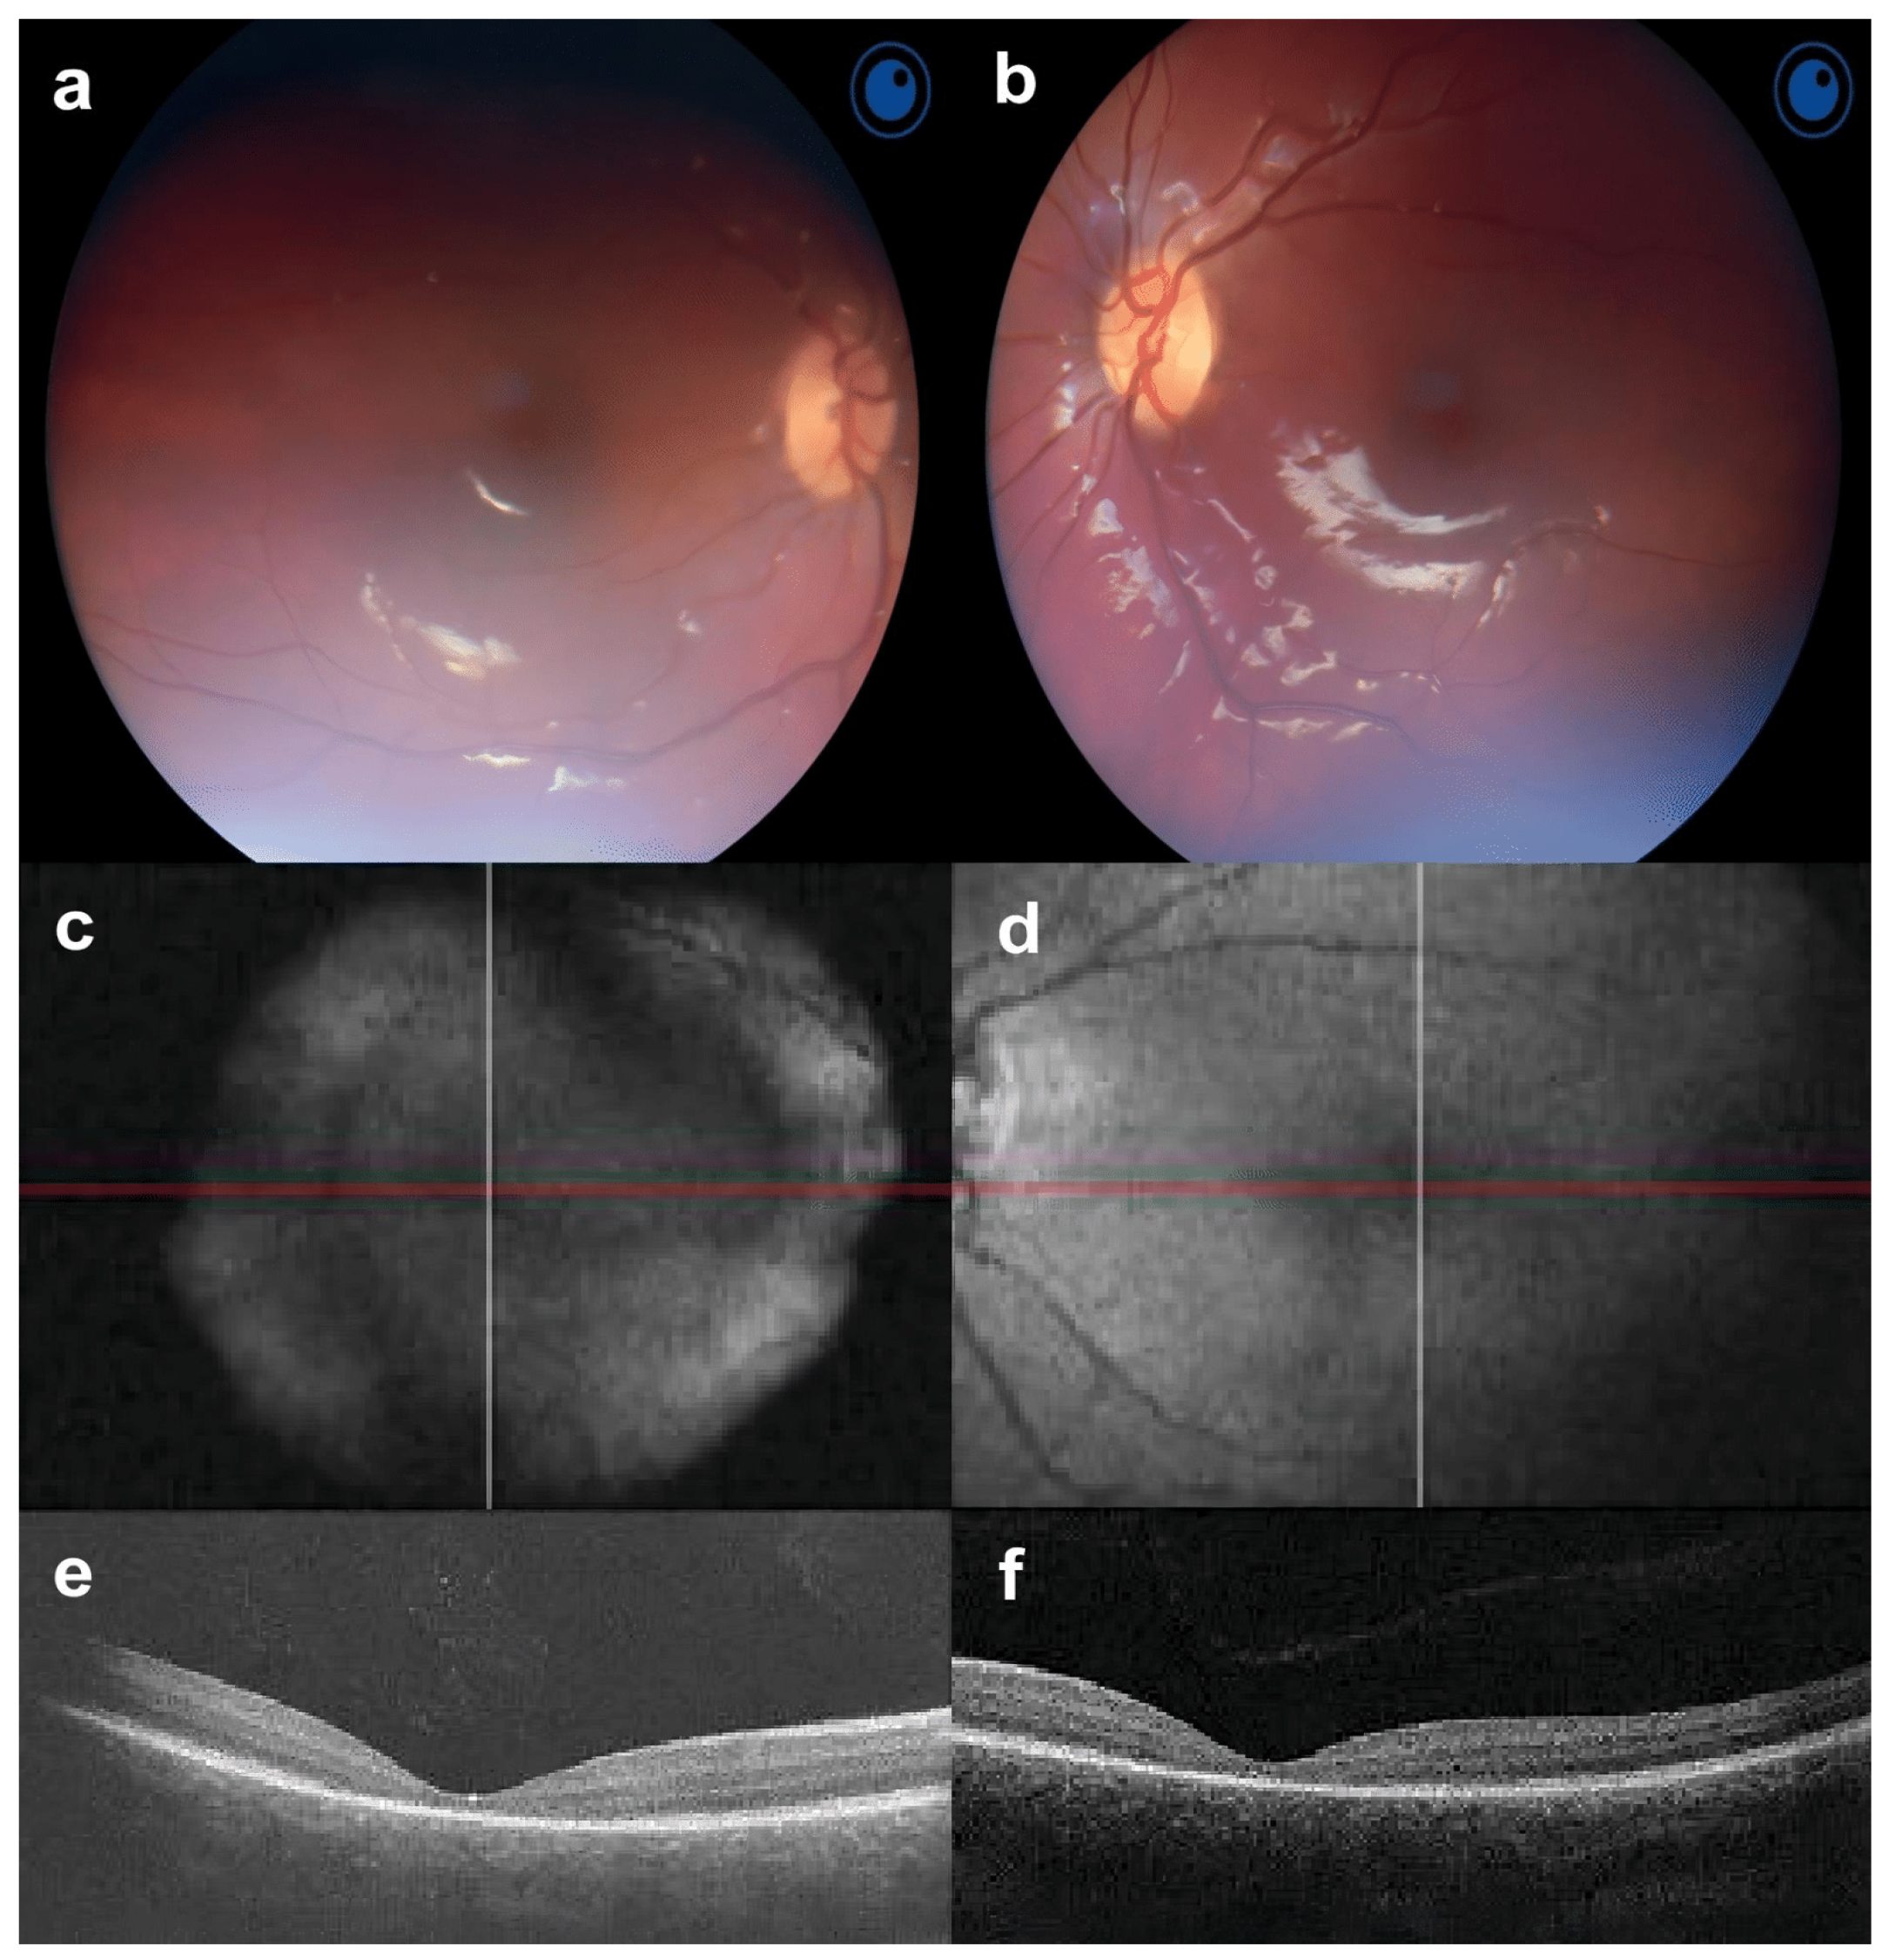

At the first examination of a 4-year-old boy (the second case), BCVA was 1.0 logMAR for both OD and OS. In addition, photophobia and hypermetropia of +1.5 diopters were diagnosed. According to the Hirschberg test, the boy had exotropia up to 10°; there were no changes in the anterior segment of the eye or the vitreous body. A fundoscopy observation revealed a standard optic disc and retinal vessel morphology (Figure 2a,b). There were no changes in the peripheral retina, while macular and foveolar reflexes were absent. According to the FAF, symmetrical abnormalities in the form of a rounded focus of hypoautofluorescence surrounded by a ring of hyperautofluorescence were noticed (Figure 2c,d). A noticeable decrease in the thickness of the neuroepithelial in the fovea was revealed; the average thicknesses in the macula were 166 μm and 169 μm for the right and left eyes, respectively. Time domain OCT also revealed the absence of a highly reflective band associated with the reflection of the conjunction of the outer–inner segment (IS/OS) of the photoreceptors. The overall average thickness of the nerve fiber layer corresponded to the age norm: 111 µm on the right, 112 µm on the left. ERG showed a decrease in the amplitude of the maximum in the cones, and the b-wave of the rod response was close to the lower limit of the normal ERG. Furthermore, a 12–15 ms prolongation of b-wave latency was observed. At the age of 8 years, an examination revealed that visual acuity had not changed, but photophobia and color vision disturbances were noted. Automatic static suprathreshold perimetry showed decreased foveal photosensitivity, an extensive central absolute scotoma, and multiple relative paracentral and peripheral scotomas. Spectral OCT data revealed a slight decrease in the average thickness of the neuroepithelium, especially in the fovea. The average neuroepithelial thicknesses were 241 µm and 255 µm for the right and left eyes, respectively. In addition to the absence of the highly reflective band, the fovea lacked myoid and ellipsoid zones. The overall average thicknesses of the retinal nerve fibers were 118 µm on the right and 120 µm on the left, which is comparable to the age norm (Figure 2e,f). Repeated ERG recording at 8 years of age found a significant decrease in the amplitude and prolongation of the latent period of the b-wave in cone and rod responses. Likewise, a decrease in the amplitude of oscillatory potentials and rhythmic ERG was observed (Figure 3).

Figure 2. Fundus photos, fundus autofluorescence (FAF) and optical coherence tomography (OCT) of the second case in both eyes. (a,b) The last fundoscopy reveals a standard optic disc and retinal vessel morphology with macular and foveal reflexes absent. (c,d) FAF presents symmetrical abnormal spots of hypoautofluorescence surrounded by a ring of hyperautofluorescence; (e,f) OCT shows a slight decrease in the average thickness of the neuroepithelium with the absence of the myoid and ellipsoid zones of the fovea.